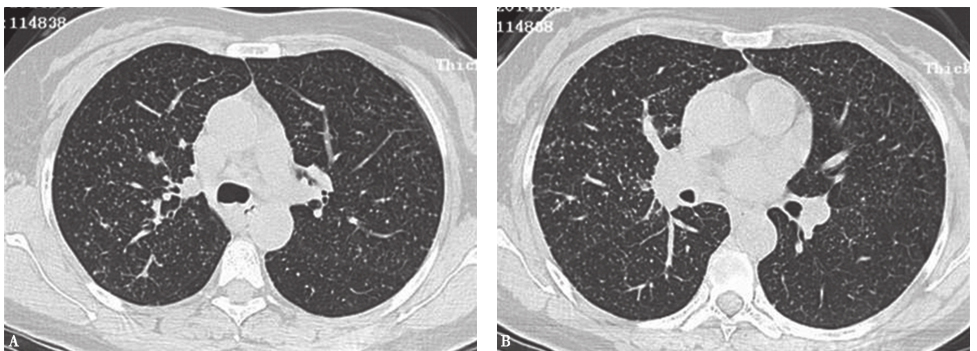

外院胸部CT示两肺散在磨玻璃影、弥漫性小结节影(图1),局部可见牵拉性支气管扩张。

图1外院胸部CT表现

两肺散在磨玻璃影及小结节影(图13),局部网状影,较入院前(图1)明显吸收、好转。